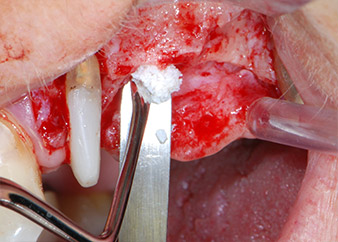

Prior to implant placement, and following verification of an intact Schneiderian membrane (Fig. 9), the internal sinus floor was augmented at both implant sites by means of xenogeneic bone substitute material (Bio-Oss, Geistlich Biomaterials) (Fig. 10).

CPITN-probe

Fig. 10: Introduction of xenogeneic bone substitute material into the implant osteotomy for internal sinus augmentation. The material was carefully condensed in an apical direction with the ball-ended CPITN probe (not shown).